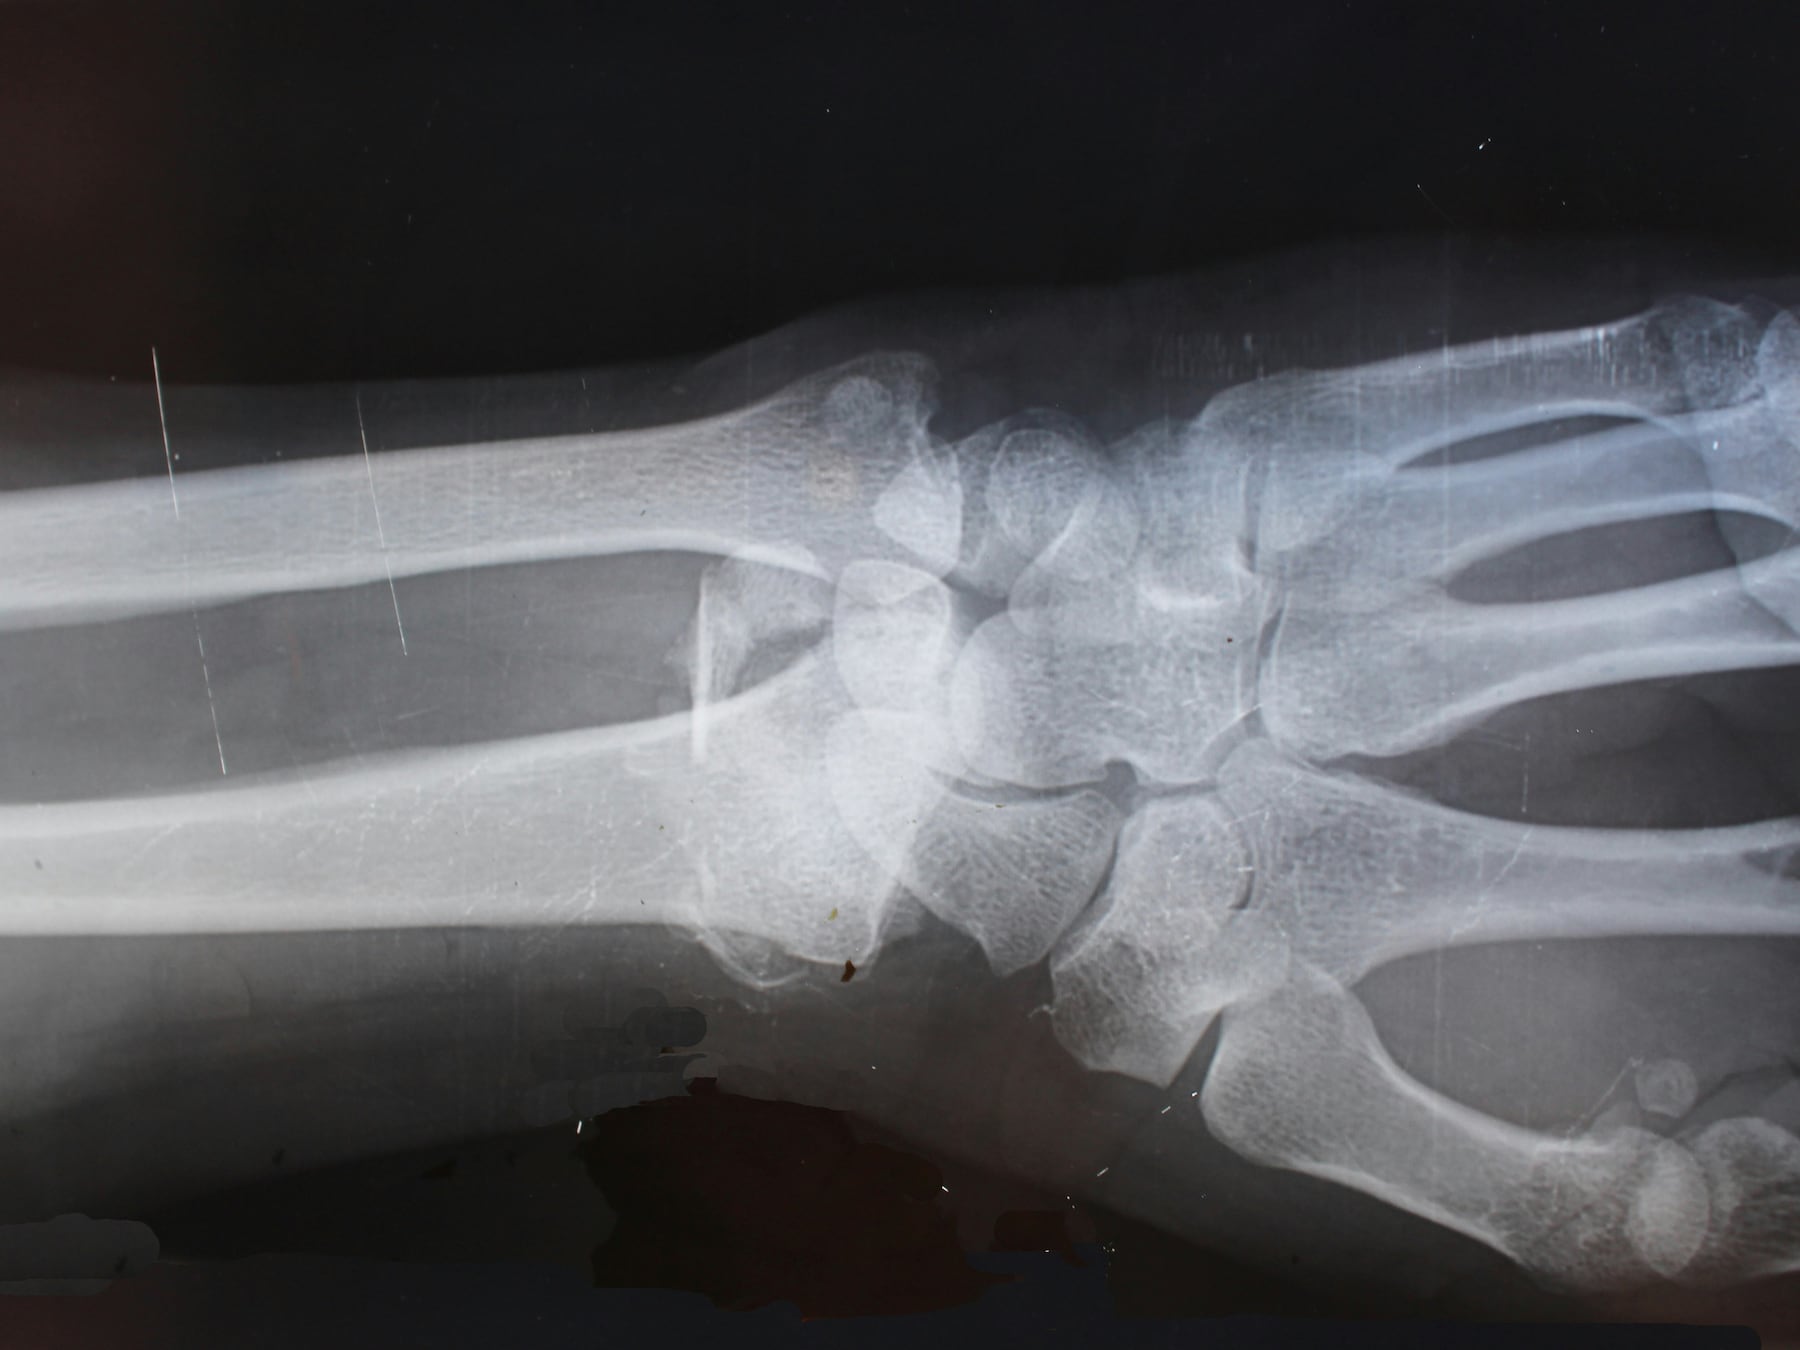

Even later klinkt een schot en schreeuwt de jachthelper het uit van de pijn. ,,De jachtpachter had hem aangezien voor een wildzwijn en haalde daarop de trekker van zijn geweer over, zo verklaarde hij later’’, vervolgt de zegsman. ,,Het slachtoffer liep een schampschot op aan zijn hand maar was desondanks zwaargewond. De aanhechting van zijn duim lag volledig open.’’